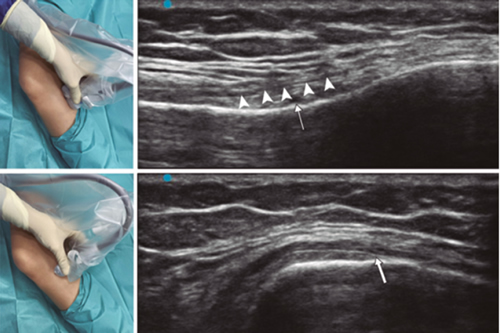

Fig. 3. Sonoanatomy and technique for performing superior medial genicular nerve block (SMGN). The transducer is located on the distal long axis of the femur and once the position of the SMGN (asterisks) is known, the probe is rotated 90 degrees to obtain a view of the femur short-axis (don't forget to keep the same depth that we find the SMGN on the long axis). VM (vastus medialis).

In order to achieve a correct location of anatomical landmarks by ultrasound we must place the patient in supine position with the knee flexed and a pillow under the popliteal fossa (14,16,19).

Fig. 4. Sonoanatomy and technique for performing inferior medial genicular nerve block (IMGN). The transducer is located on the proximal long axis of the tibia and we identify the vasculonervious package of the IMGN (arrow) just below medial collateral ligament (arrowheads). Then the probe is rotated 90 degrees to obtain a short-axis view of the tibia (don't forget to keep the same depth as the IMGN found on the long axis).

After performing knee asepsis/antisepsis, surgical field placement, and the sterile sheath of the high frequency linear transducer, we proceed to locate the SMGN (Figure 3). Placing the probe in a coronal plane on the inner face of the knee, we slide it cranially to visualize the junction of the metaphysis to the femoral diaphysis and the superior medial genicular artery/nerve (ASMGN), usually located near the periostium of the femur (if this neurovascular structure is not found, the junction between metaphysis and femoral diaphysis is taken as a reference). The mid-point of the transducer corresponding to ASMGN is then marked on the skin and the transducer is rotated to be placed in the transverse or axial plane to view ASMGN on the short axis (if this structure is not visible, confirm that we are at 50 % depth of the femur). In this cross-section the needle of the TRF is advanced in plane from anterior to posterior toward the ASMGN or to a depth of 50 % of the thickness of the femur. Finally, the transducer is rotated 90° again, leaving it in a coronal plane to check that the needle tip is near the ASMGN or the junction of the metaphysis and femoral diaphysis (14,16,19).

To locate the IMGN (Figure 4), we placed the transducer in a coronal plane on the inner face of the knee, sliding it caudally to identify the diaphysis junction with the tibial metaphysis and the inferomedial genicular artery/nerve (AIMGN). And we repeat the same steps we used for SMGN. If the AIMGN is not found, the reference to be taken shall be the depth of 50 % of the thickness of the tibia (14,16,19).